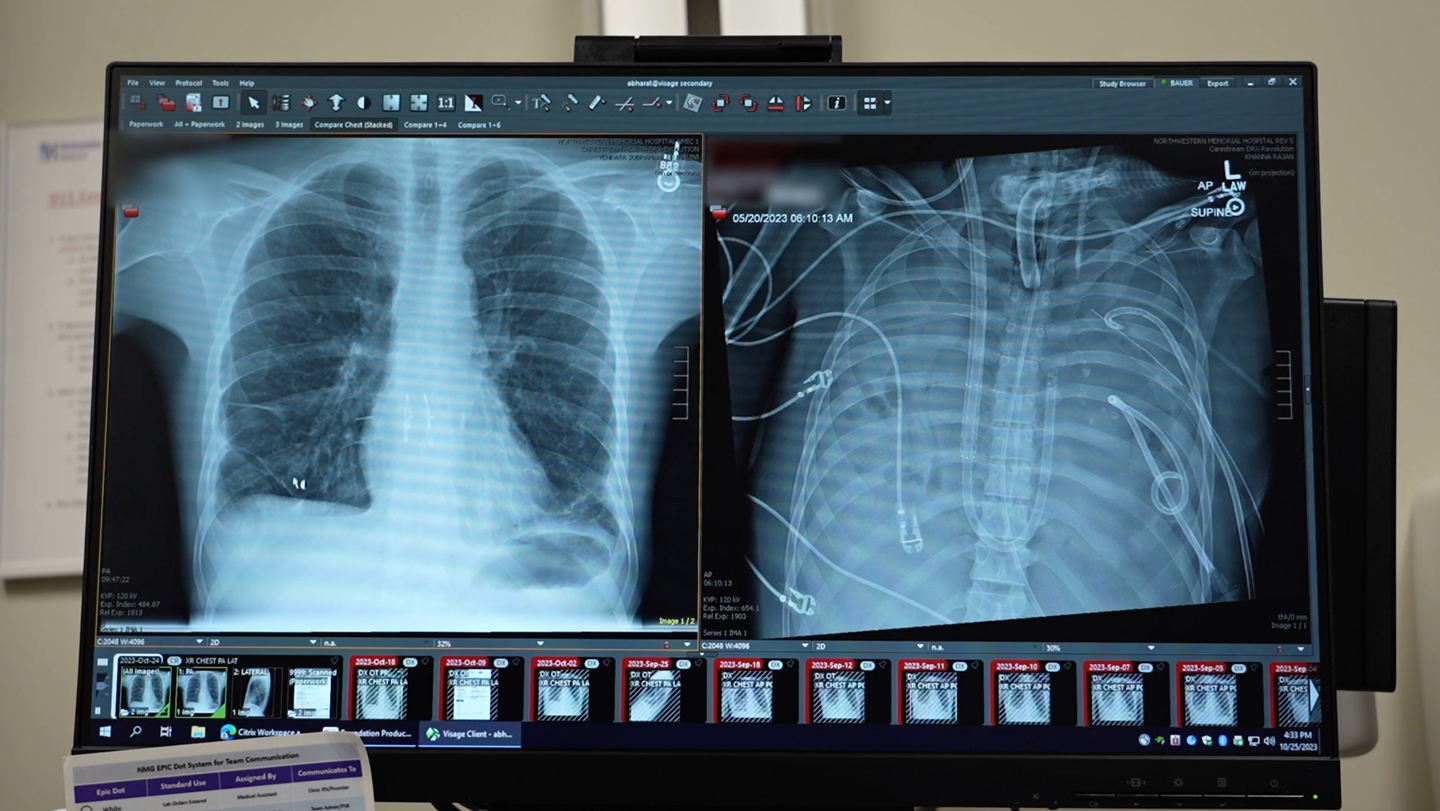

The path wasn’t straightforward. Lung transplants are uncommon miracles, but they’re delicate. With infections like Alex’s active Pseudomonas in his system, no transplant center would risk it – the bacteria could kill the donor lungs instantly. Yet, leaving him on a ventilator wasn’t sustainable; his damaged lungs couldn’t handle it. Bharat, a seasoned surgeon skilled in transplants for patients ravaged by COVID-19 or similar scourges, knew they needed something radical: remove the lungs entirely and keep him alive artificially until an organ became available. This inspired the creation of a custom artificial lung system, a feat of engineering and medicine that could sustain life in ways conventional tech couldn’t. Visualizing it, Bharat saw tubes, shunts, pumps – devices to draw blood from the right side of the heart, oxygenate it by stripping out carbon dioxide just like natural lungs, and then shunt it back to the heart’s left side for circulation. It was proof-of-concept turned into a life-saving procedure. For Alex, it was hope. His family clung to updates, praying for his pain to end. The doctors felt the weight too; one wrong move and he’d be gone. But in the chaos of intensive care, with beeps and alarms, Bharat’s team prepared, driven by a shared belief that innovation could rewrite Alex’s ending. They weren’t just removing lungs; they were bridging a gap between death and rebirth, transforming cold machinery into a conduit for human resilience.

Delving into how this artificial lung system worked reveals its brilliance and humanity. Unlike earlier attempts with extracorporeal membrane oxygenation (ECMO), a form of life support that pumps oxygenated blood but often strains the heart, this setup truly mimicked the lungs’ double role: oxygenation and proper cardiac support. Picture it – blood exits the right atrium, gets pumped through an oxygenator to refresh it, removing evil carbon dioxide and infusing life-giving oxygen, then flows seamlessly back to the left atrium. Pumps handled the flow, ensuring the heart didn’t overwork. In the operating room, surgeons crafted this like artists: shunts to channel blood, tubes to connect vessels, all orchestrated to keep Alex’s body functioning as if his lungs were intact. For Bharat, it was a testament to collaboration between engineers and doctors, turning abstract designs into tangible saviors. Alex, under anesthesia, couldn’t feel the procedure, but post-op, he must have sensed a strange stability, his body humming along mechanically. The team monitored every beat, every saturation level, their faces etched with tension and hope. It wasn’t just machines; it was a symphony of precision, where one glitch could shatter the harmony. This system, reported in Med on January 29, proved a true artificial lung could buy time, keeping patients alive until transplants. For Alex, it was a bridge over turbulent waters, whispering that survival was possible. His nurses, caring hands in the night shifts, checked vitals with quiet encouragement, turning the sterile ICU into a space of unspoken support.

The 48 hours that followed were a marathon of anticipation. With Alex’s diseased lungs removed and the artificial system in place, doctors watched as his infected right side of the heart began to heal shockingly fast. Contrary to expectations of weeks for the bacteria to clear, removing the bacterial breeding ground – the lungs – sped recovery like wildfire doused by water. Infections vanished as if evicted. Meanwhile, the transplant list beckoned anew. Alex’s bloodwork improved, his body stabilized. Worry crept in during that limbo; what if an organ didn’t arrive? His loved ones visited, holding his hand, sharing stories to keep his spirit alive. Bharat recalls the quiet nights, the team sipping bad hospital coffee, debriefing tirelessly. Then, fortune smiled: an organ matched immediately, a gift from a donor’s legacy. The transplant surgery unfolded smoothly, lungs reattached, blood flowing naturally once more. Now, over two years later, Alex thrives. His heart beats strong, lungs function normally – he’s back to work, family time, life’s simple joys. Doctors marvel at his progress, a living testament to medical ingenuity. Yet, beyond stats, it’s the human cost that lingers: Alex’s gratitude, perhaps shared in quiet moments; the donor family’s solace knowing lives like his were saved; Bharat’s satisfaction in mending what seemed broken.